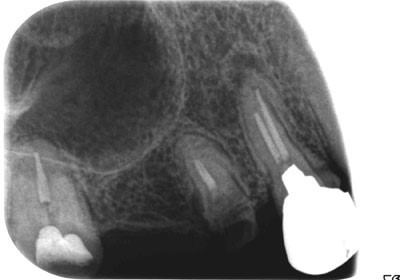

症例1

治療前

主訴 左上小臼歯から大臼歯部にかけて、脱離・歯冠崩壊、及び欠損があり、左奥では物が噛めない。

まだ年齢も50代と若く、義歯は煩わしく嫌であるという訴えがあり、左上5番・6番にインプラントを2本埋入する計画を立案。

副鼻腔までの距離がわずかしかないので、ソケットリフトと、骨の緻密化を計る為に、C・C・Wドリリング法を併用。

オぺから仮歯装着まで3ヶ月を要し、4ヶ月未満の治療期間を経て最終補綴物ジルコニア2本を装着。

リスクとしては、ソケットリフト(骨造成)による一過性の副鼻腔炎が起きる可能性がある。まれに洞底膜が破れる可能性がある。

ただし、膜は約3週で再生するので、膜の回復を待ち、再オペを行う。

費用 116万(オペ・ソケットリフト・人工骨・採血による濃縮血小板生成・仮歯・最終補綴物まで含む)